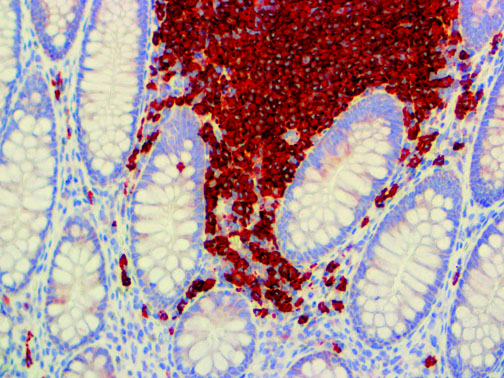

Clinical and laboratory manifestations of HLH include fever, enlarged liver and/or spleen, neurologic dysfunction, coagulopathy, liver dysfunction, cytopenias (i.e., low levels of erythrocytes, leukocytes, and/or platelets), hypertriglyceridemia, hyperferritinemia, hemophagocytosis, and eventually diminished NK cell activity as the immune system becomes progressively paralyzed. HLH can be familial (primary HLH) or secondary to another disease process (sHLH), such as rheumatic disease, in which it is referred to as macrophage activation syndrome (MAS, characterized by elevated ferritin).

This activation induces inflammatory monocytes to highly express IL-6, starting a localized and then systemic cascade effect that results in hyperproduction of IL-6, which accelerates the inflammatory process. Because IL-6 also increases vascular permeability, excessive levels cause blood vessels to become very leaky. This, along with clotting factors released from vascular endothelial cells, stimulates the coagulation cascade, resulting in microthrombosis (tiny clots), which leads to ischemia and tissue death of the kidney, intestines, heart, liver, brain and extremities.